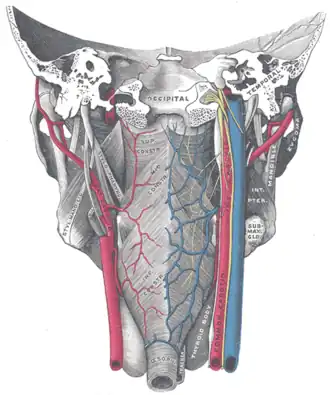

Muscles of the pharynx, viewed from behind, together with the associated vessels and nerves. (Inf. const. labeled at bottom center.) | |

Killian's dehiscence (also known as Killian's triangle) is a triangular area in the wall of the pharynx between the cricopharyngeus (upper esophageal sphincter (UES)) and thyropharyngeus (Inferior pharyngeal constrictor muscle) which are the two parts of the inferior constrictors (also see Pharyngeal pouch). It can be seen as a locus minoris resistentiae. A similar triangular area between circular fibres of the cricopharyngeus and longitudinal fibres of the esophagus is Lamier's triangle or Lamier-hackermann's area.